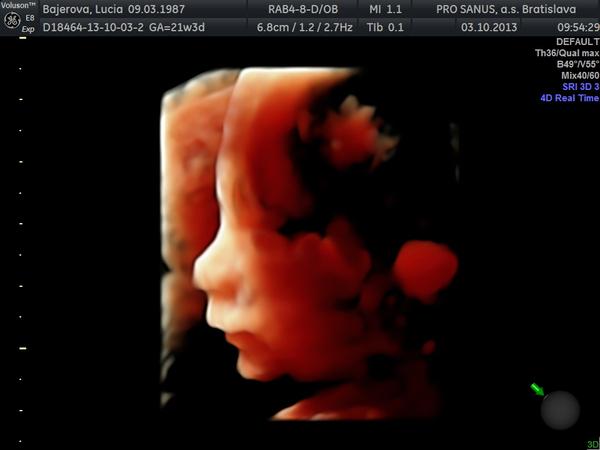

@lucya87 krááásna foto